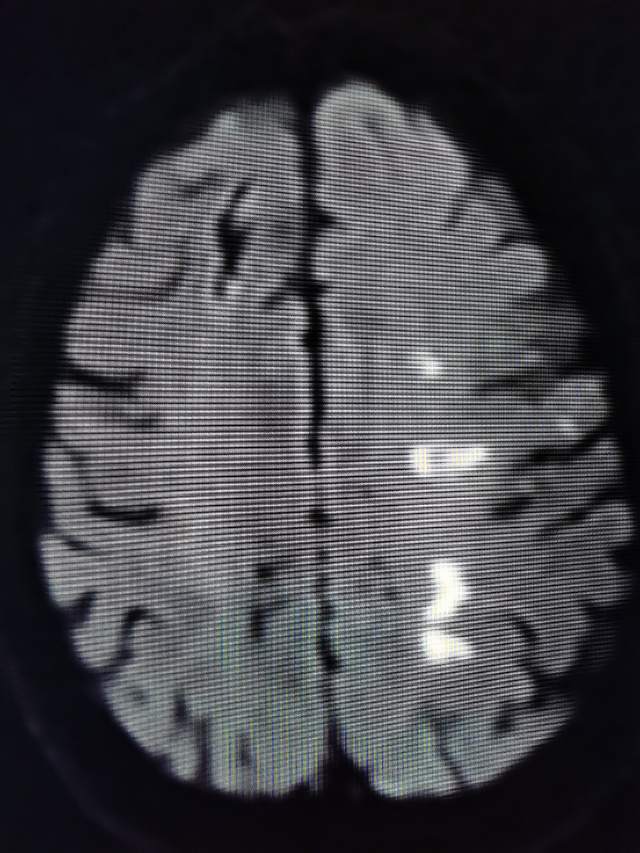

70岁老年男性,3个月前急性脑梗塞,尽管缺血性发作后及时在医院给予了“静脉溶栓”、药物和康复治疗,3个月后仍然存在言语含糊、头胀、记忆力减退和右侧上肢肌力减退,还伴有间断心悸等表现。初步的影像学检查发现左侧大脑中动脉M2段重度狭窄。家属一直彷徨在外科干预和药物保守治疗的选择中,干预吧,怕出现意外;

不干预吧,毕竟残存了一些功能障碍,还可能存在再次卒中的风险。通过多学科诊疗(MDT)和脑血管造影(金标准)后,进一步确认了狭窄的存在,左侧大脑中动脉上干血管存在重度狭窄,下干轻度狭窄。手术的难度在于狭窄的部位处于血管弯曲的部位,另外还要为下干预留日后可能干预的空间。